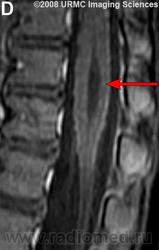

МРТ.  Терминальный желудочек

http://www.radsource.us/clinic/0807